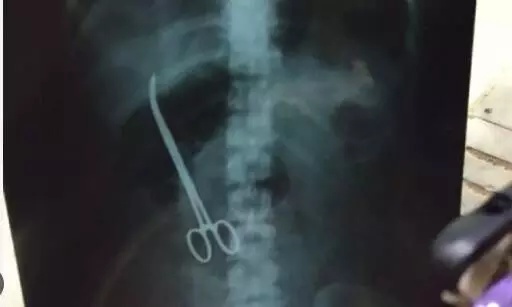

పెద్దపల్లి జిల్లా గోదావరిఖనిలో వైద్యుల నిర్వాకం బయటపడింది. ఆరేళ్ల క్రితం డెలివరి కోసం వెళ్లిన ఓ మహిళ కడుపులో కత్తి ఉంచి కుట్లు వేశారు వైద్యులు. అప్పటి నుంచి బాధితురాలు కడుపునొప్పితో బాధపడుతుంది. ఎంతకు తగ్గకపోవడంతో హైదరాబాద్లోని ఓ ఆస్పత్రికి వెళ్లిన బాధితురాలికి విస్తుపోయే విషయాలు తెలిశాయి. స్కానింగ్ రిపోర్టులో కడుపులో కత్తి ఉన్నట్లు తెలియడంతో ఆ మహిళ అవాక్కైయింది.

కుటుంబ సభ్యుల ఆదోళనతో వైద్యులు దిగొచ్చారు. బాధితురాలికి కొంత డబ్బు చెల్లించడంతో పాటు వైద్య ఖర్చులు భరిస్తామని ఒప్పందం చేసుకున్నారు. ఈ ఘటన వెలుగులోకి రావడంతో పలువురు ఆగ్రహం వ్యక్తం చేస్తున్నారు. డెలివరి కోసం వచ్చిన మహిళ కడుపులో కత్తి మర్చిపోయిన వైద్యులపై కఠిన చర్యలు తీసుకోవాలని డిమాండ్ చేస్తున్నారు. ఇలాంటి వైద్యుల వల్లే అమాయకుల ప్రాణాలు పోతున్నాయి ఆగ్రహం వ్యక్తం చేస్తున్నారు. వైద్య సేవల్లో నిర్లక్ష్యంగా వ్యవహరిస్తున్న వారిపై చర్యలు తీసుకోవాలని డిమాండ్ చేస్తున్నారు.